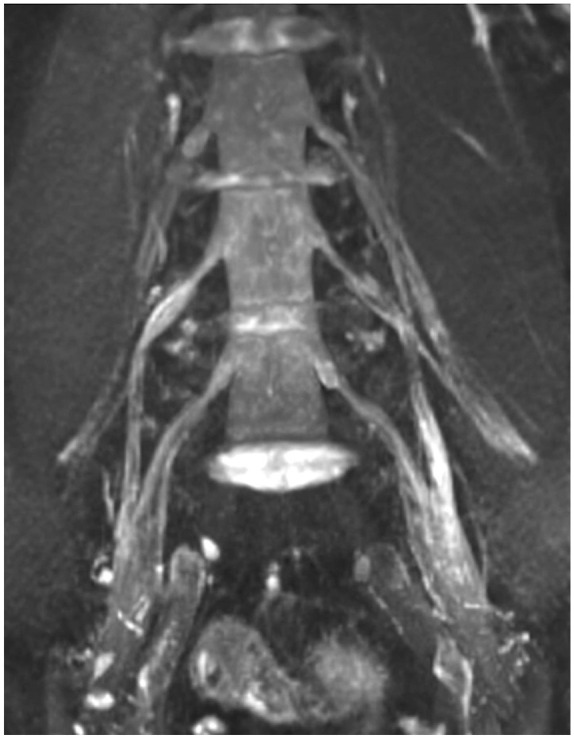

Methods and design: We longitudinally examined 12 CIDP patients from 2016 to 2022 using NUS, MRN, nerve conduction studies (NCS), and clinical parameters (inflammatory neuropathy cause and treatment (INCAT)/overall disability sum score (ODSS)). NUS evaluated the cross-sectional area (CSA) of the median, ulnar, radial, tibial, fibular, and sural nerve as well as the intranerve CSA variability (INVcsa) of the tibial, fibular, ulnar, and median nerve, whereas MRN evaluated T2-weighted sequences of the fibular and tibial nerve at the popliteal fossa.

Results: Five patients showed clinical improvement/stability with corresponding improved or stable NCS/NUS parameters (number of nerves with increased CSA and INVCSA). Seven deteriorating patients showed deteriorating NCS and either increasing or decreasing NUS markers possibly indicating inflammatory activity or degenerative CSA reduction. The difference ΔINCAT/ODSS2022-2016 correlated positively with NUS ΔINVCSA2022-2016 (p = 0.007, r = 0.731, n = 12) and with NUS ΔCSA2022-2016 of the tibial nerve (p = 0.0005, r = 0.865, n = 12). Further, NUS-CSA of the tibial nerve in the popliteal fossa in 2016 correlated inversely with the difference of the INCAT/ODSS score (ΔINCAT/ODSS2022-2016; r = -0.653; p = 0.033; n = 11). Finally, the Bland-Altman analyses for the tibial and fibular nerve showed a bias of -1.903 and 2.195 mm2 (bias = NUS-CSA - MRN-CSA) accordingly revealing a difference between MRN and NUS measurements for deeper nerves.

Conclusion: CSA and INVCSA of the tibial and fibular nerve can be used for monitoring in CIDP, and increased CSA of the tibial nerve is a good prognostic marker. MRN is more reliable for evaluating inflammation in proximal leg nerve segments.